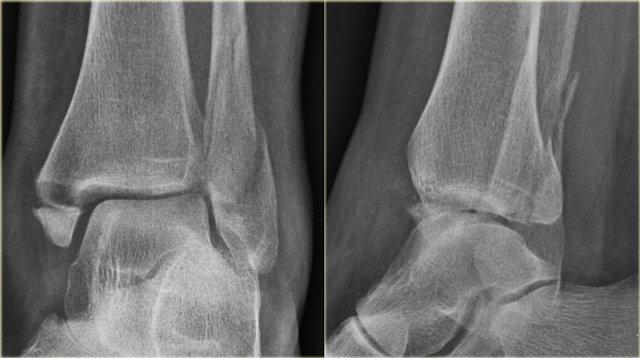

Stage 1

Các hình ảnh cho thấy gãy xương loại Weber A điển hình.

Tất cả đều là gãy xương giai đoạn 1.

Giai đoạn 2 cực kỳ hiếm gặp.

Chú ý hướng nằm ngang của các đường gãy.

Đây là các gãy xương kiểu giật đứt do kết quả của sự bong gân giật.